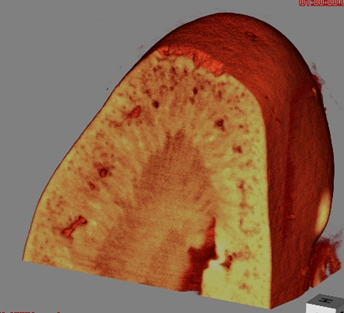

マウス腎臓

屈折コントラスト法

(DE)

17.8 keV

2時間

密度分解能〜1 mg/cm

3

試料提供:北里大学Lwin准教授